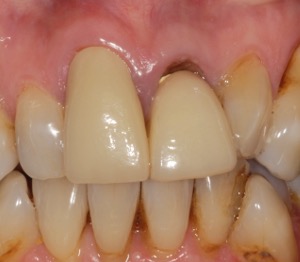

Single implant crowns

Single implant crowns are an excellent way to replace missing teeth. They do not damage the neighbouring teeth and last for a long period of time. These are usually screw retained to allow repair/replacement if there are any maintenance issues.